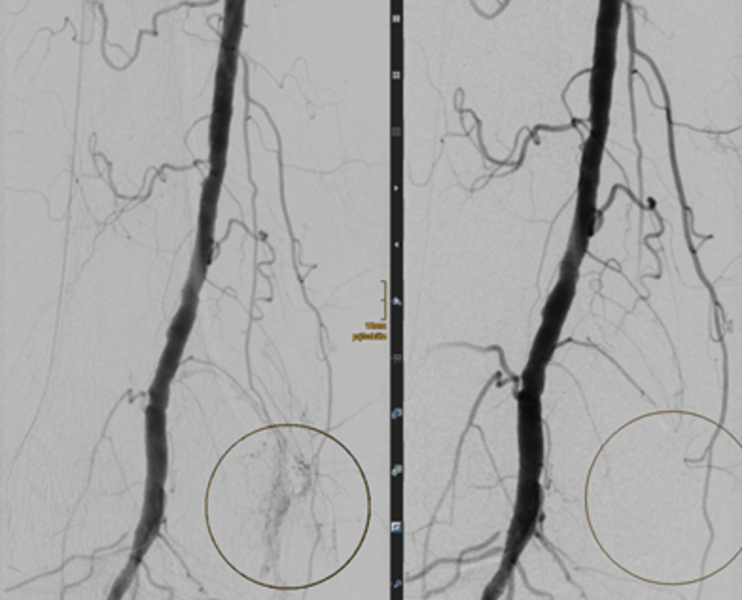

Erfolgreiche TAPE bei schmerzhafter Kniegelenkarthrose einer 88-jährigen Patienten. Durch die superselektive Embolisation der oberen Kniegelenkarterie wurde die entzündliche Mehrdurchblutung blockiert (siehe Kreise, links vor Embolisation, rechts nach Embolisation), woraufhin die Schmerzen nachließen.